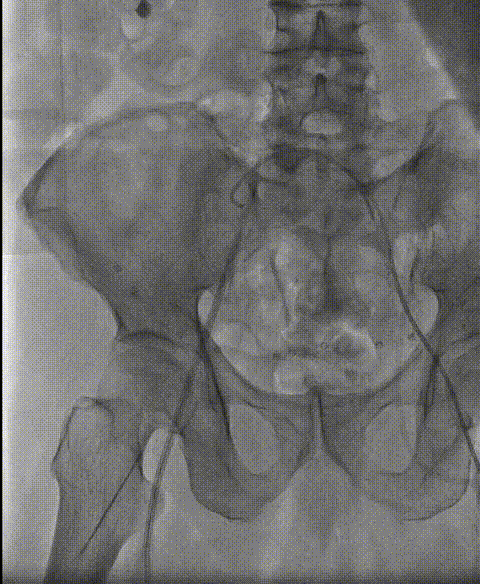

入路情况:右股主入路,斑块较大,轻柔操作

入路造影评估 正中穿刺